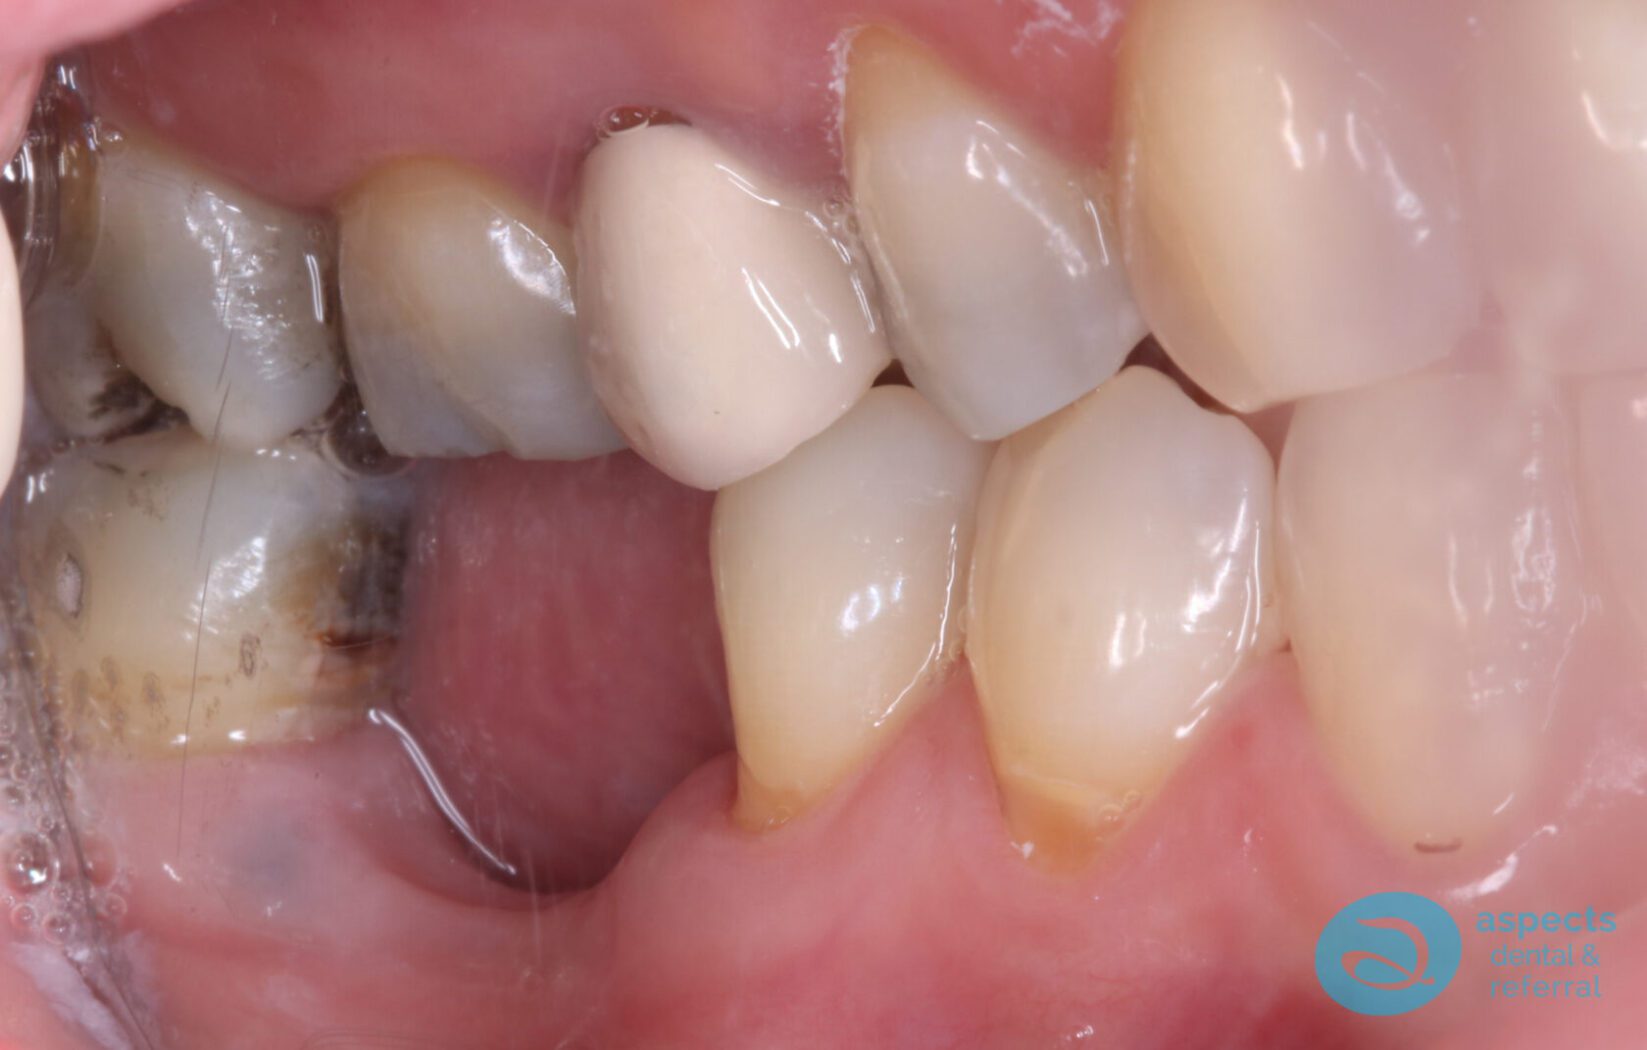

Our Dental Patient presented with a failing Root Canal-Treated Tooth with recurrent infection. Due to the persistent infection and poor prognosis, the tooth was extracted.

Before Dental Implant Photo